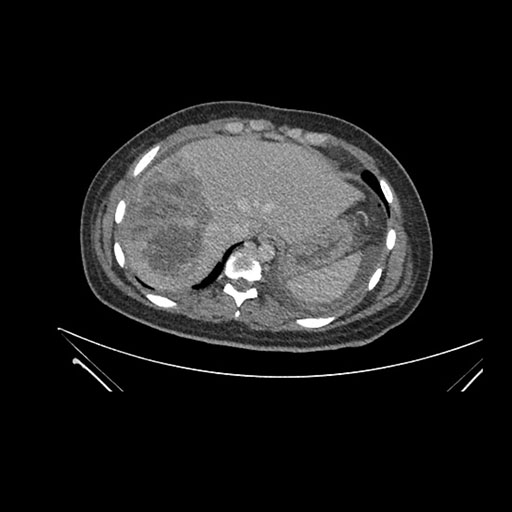

Imaging Analysis

Look through the patient's CT scan to identify any areas of concern for the necessary procedure.

Axial Arterial

Based on initial findings, which issue(s) would you be most concerned about?